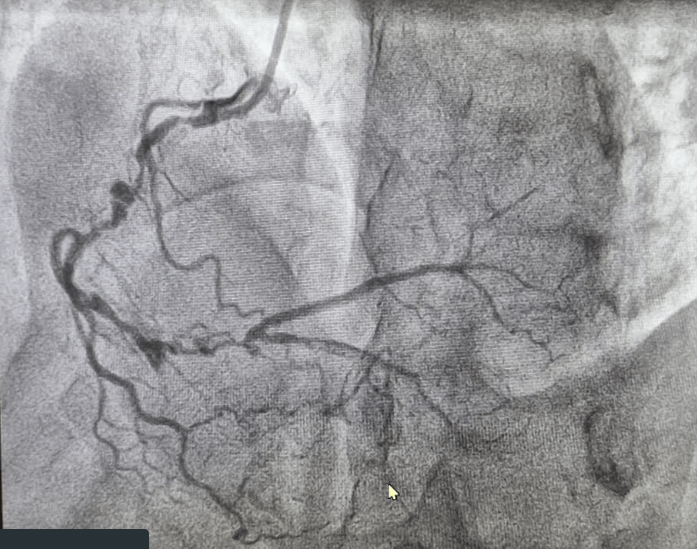

Findings of CAG

• Patient has extensive triple vessel disease with total occlusion of mid LAD. LCX diffuse 90% & RCA diffuse 90% stenosis & distal RCA total occlusion.